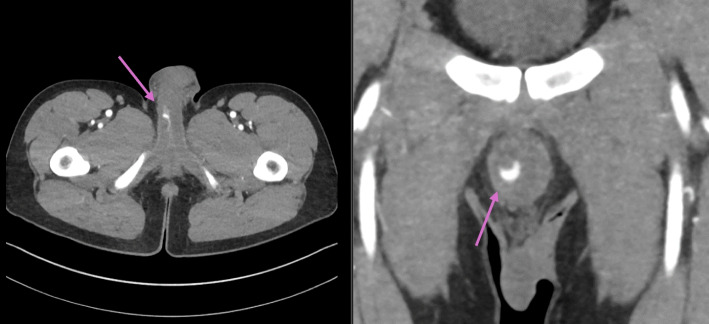

A healthy 24-year-old male patient presented with a history of straddle-trauma from a bicycle accident and concomitant non-ischemic-priapism lasting for ten days. On a contrast-enhanced computed tomography scan an arterio-cavernous fistula establishing a connection between the right cavernosal artery and the ipsilateral corpus cavernosum was diagnosed. Super-selective unilateral arterial embolization was performed using gelatin sponge and microcoils. Technical success became evident with the consecutive detumescence of the penis and long-term preservation of baseline urogenital functions.

一位24岁的健康男性患者,有自行车事故造成的跨骑创伤史,并伴有持续10天的非缺血性阴茎勃起。在对比增强的计算机断层扫描上,诊断出动脉-海绵体瘘,建立了右海绵体动脉和同侧海绵体之间的连接。采用明胶海绵和微线圈对单侧动脉进行超选择性栓塞。技术上的成功是显而易见的,阴茎的连续消肿和长期保存基线泌尿生殖功能。